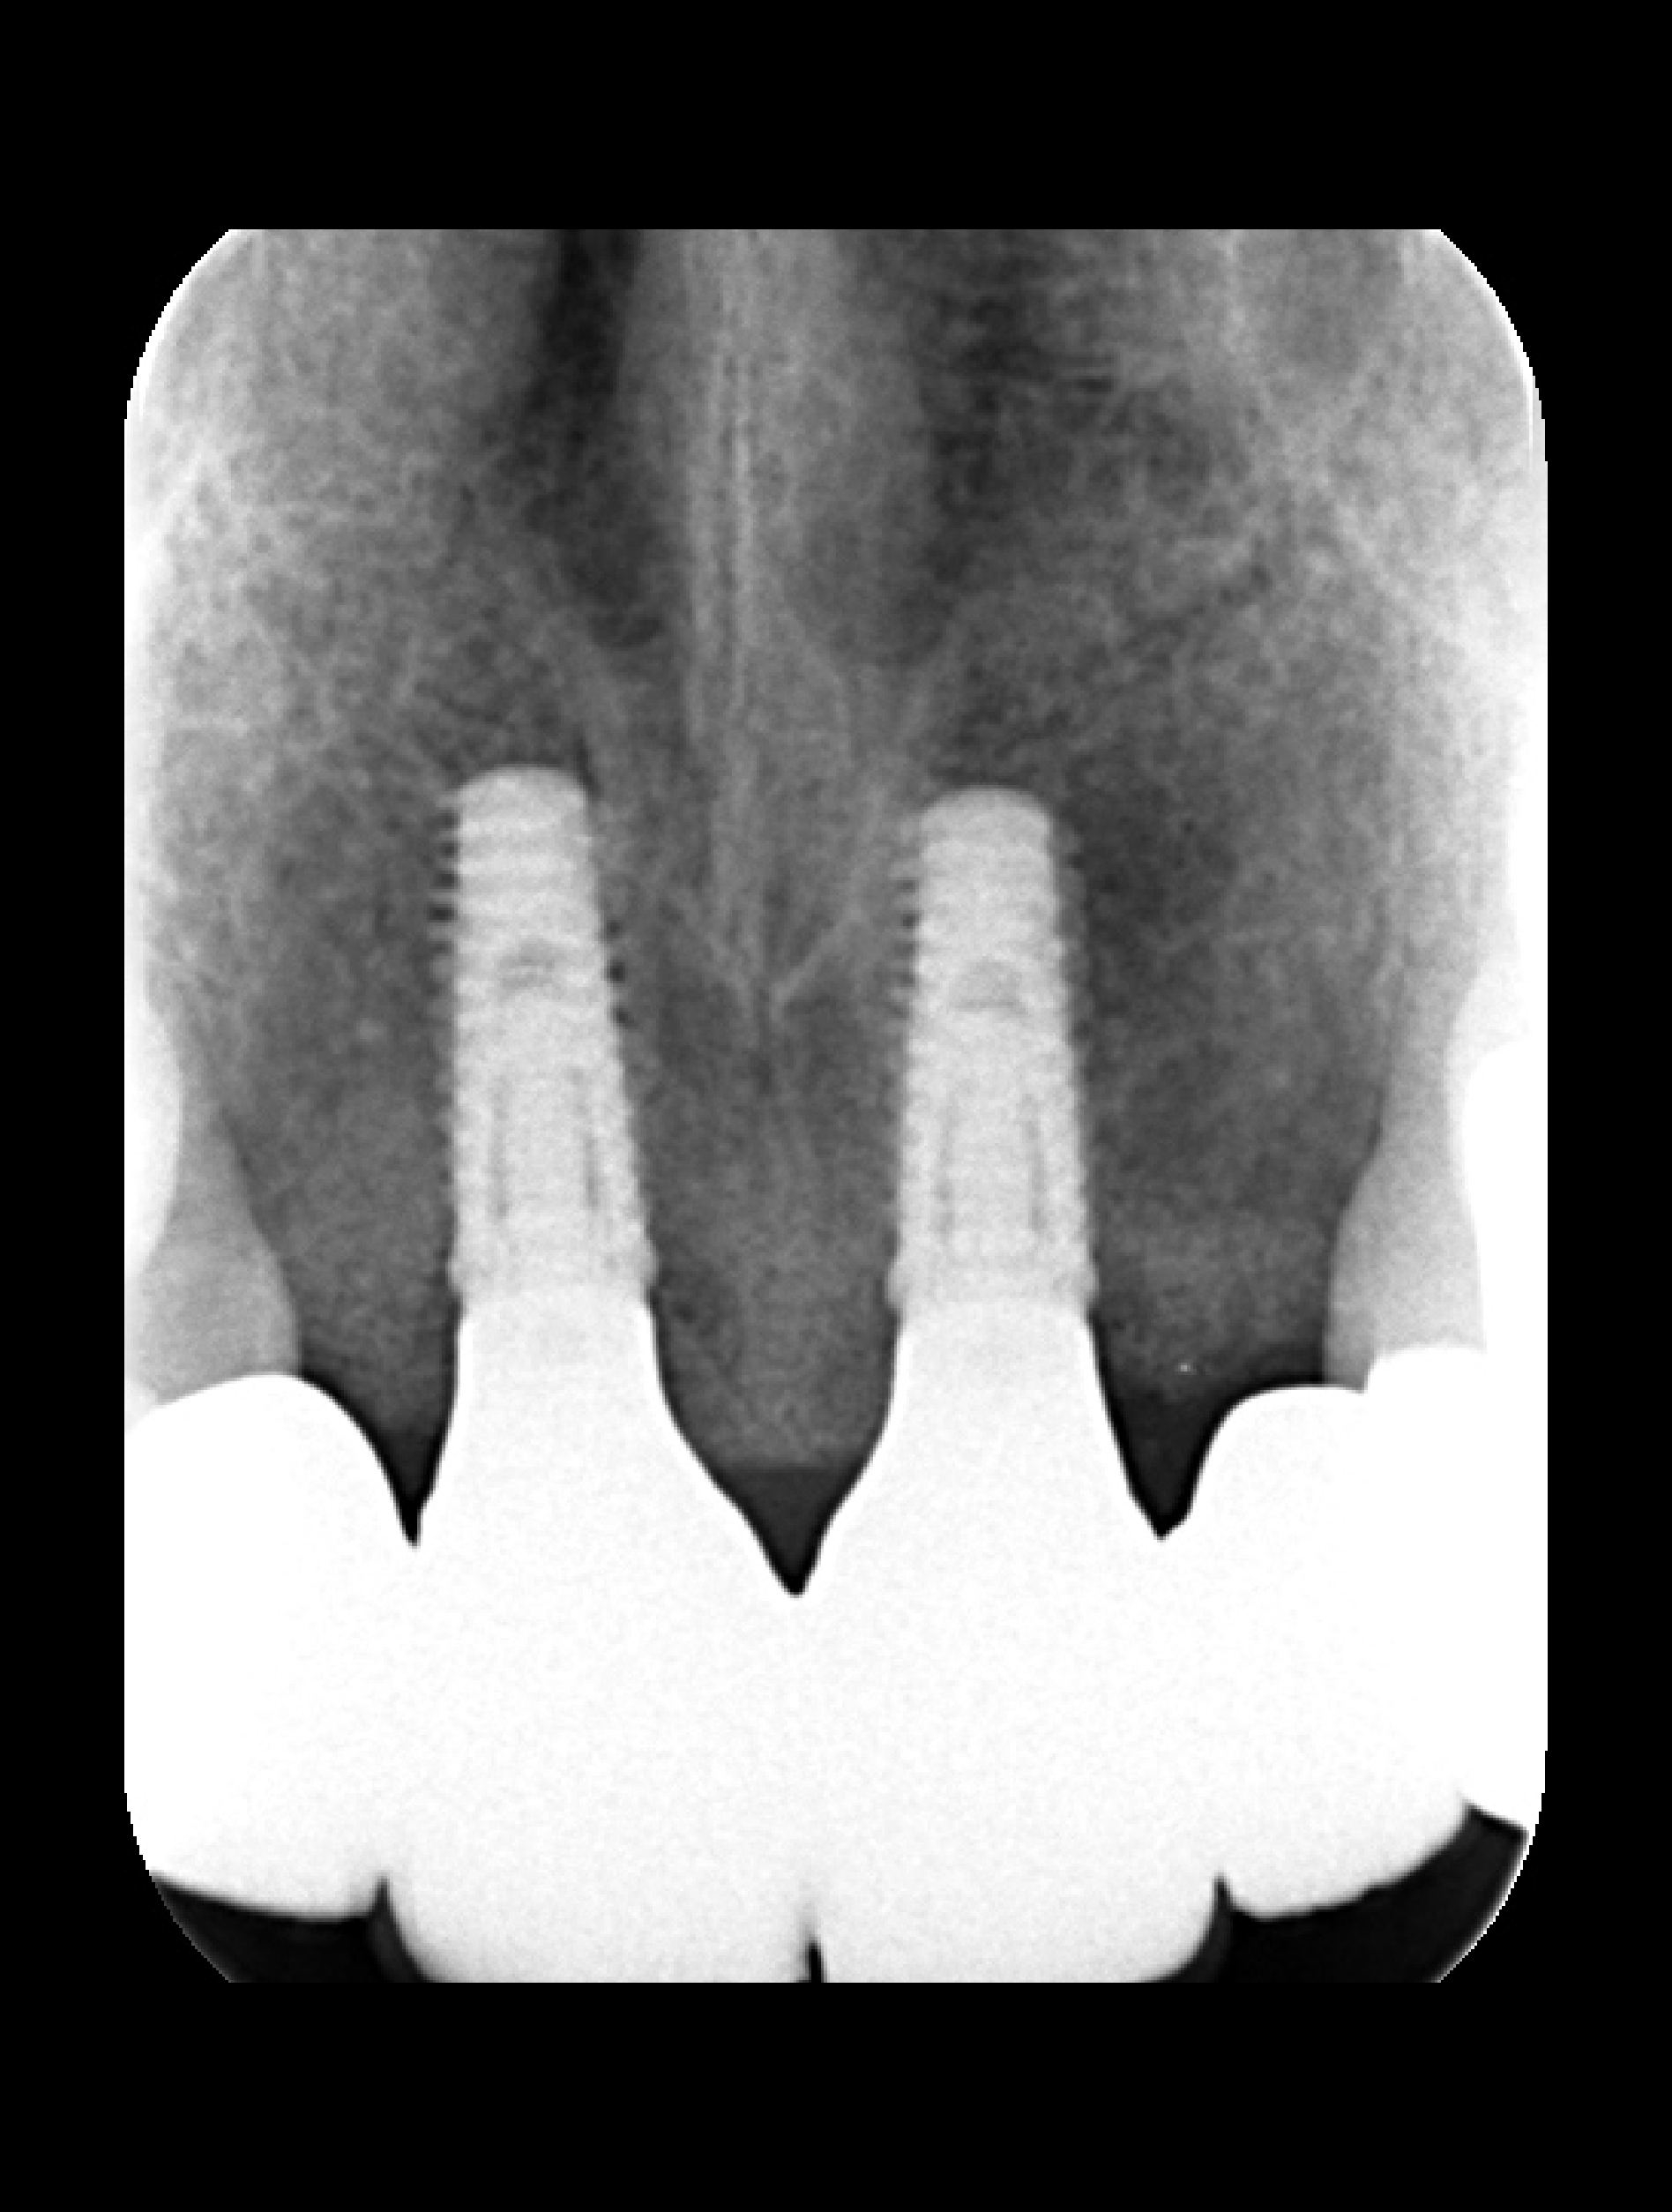

骨造成・歯肉移植を伴うインプラントのやり直し症例

Before

After

年代

40歳代

主訴

前歯5本をやりかえたい。

背景

小学生の頃に転んで前歯を折ってしまってずっと前歯で苦労してきた。

治療

旧インプラント撤去・骨造成・歯肉移植・インプラント治療・セラミック治療

治療期間

1年6ヶ月

治療費用

1,870,000円(税込)